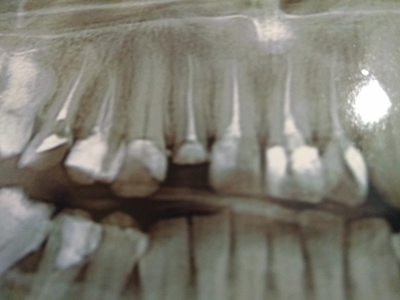

Сломался зуб, почти под самую десну.

На мои слова о том, что может сразу имплант ? Закатывают глаза "ну если вы так хотите, то можна и так" Но я же блин пришел к спецам. Если зуб был дважды пломбирован и сломался, то корни уже не лучшие.